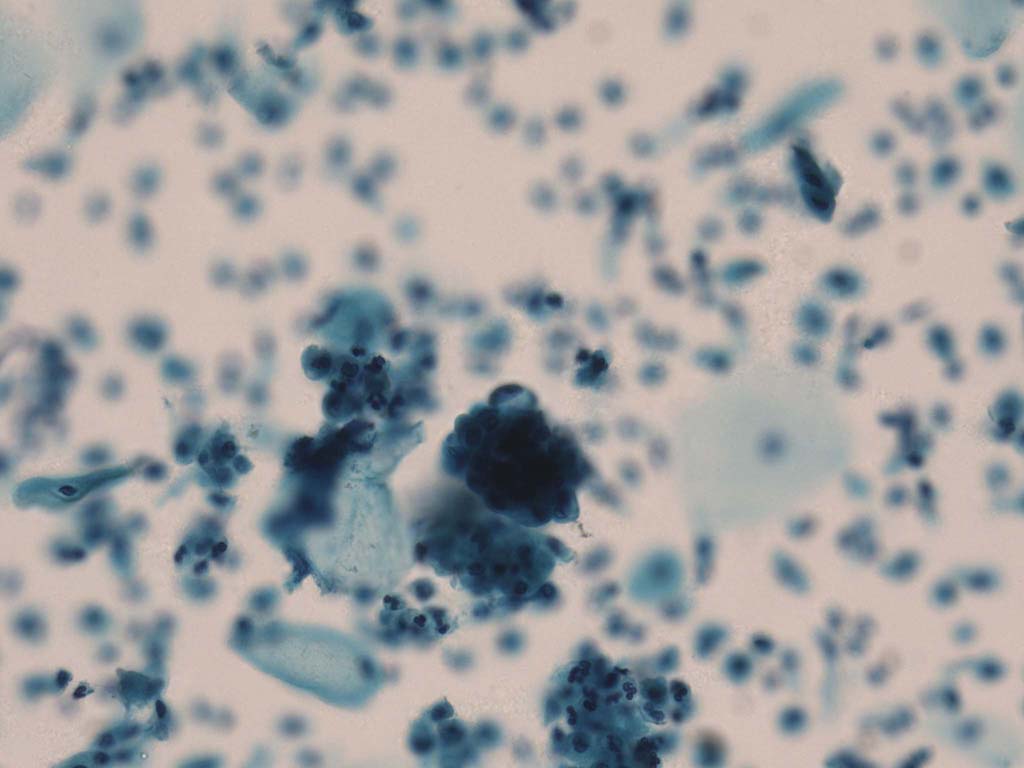

A good image fusion method should contain the following properties. First, it preserves both the details of small size objects and the integrity information of large size objects in the fused image, even in the case of the size of the interested objects varying largely in the image. For example, the cervical cell images from the microscope contain both small size isolated cells and large size agglomerates, which are both useful for cervical cytology [5]. Second, it should be efficient enough to handle large-scale data. For instance, it needs to process thousands of fields of view (FoV) in an acceptable time for the whole slide scanning in digital cytopathology [6], which requires to fuse a series of high resolution images captured at each FoV in a very efficient way. Third, it does not produce obvious artifacts. Despite being studied extensively, to our best knowledge, existing fusion methods may not meet these requirements simultaneously.

To demonstrate the effectiveness and efficiency of the proposed image fusion method , we conduct a set of comparative experiments on three image datasets. The first is composed by 8 pairs of multi-modal medical images and the second one contains 15 pairs of multi-focus gray or color natural images. These two datasets are often used in many related papers and some examples are shown in Figure 3(a) and Figure 3(b). The third one is a new multi-focus cervical cell image dataset collected by ourselves, which consists of 15 groups of color images and each group contains a series of multi-focus cervix cell images with size of or , etc. Some source examples are shown in Figure 3(c). Our source code implemented in C++ along with the new multi-focus cervical cell image dataset is available online.

Figure 9, Figure 10 and Figure 11 show the comparative fused results of the multi-focus cell images shown in Figure 3(c). For clarity, we also present a closeup view in the right-bottom of each sub-picture in Figure 9 and Figure 10. As shown in the close-up views of Figure 9, the fused images based on DSIFT, IM, MWGF and BF methods are extremely blurred in the boundary and fail to keep the details of cell nucleus. Furthermore, the DTCWT and NSCT based methods produce halo artifacts in the fused images, while GFF and CNN based methods fail to preserve the small cell nucleus. LP-SR based method nearly works fine which keeps the most of the details of the small size cells, but the integrity of the clustered large size cells is damaged. Fortunately, in our proposed method, the integrity of the clustered large size cells is preserved and most of the isolated small size cells are maintained from the original images, which demonstrates the best visual quality.

Similarly, as shown in the close-up views of Figure 10, the fused images from DSIFT, IM, MWGF and BF are blurred and lose some nucleus details, while the results from DTCWT, GFF, CNN and NSCT produce halo artifacts. LP-SR based method can keep details well but also produces halo artifacts and other noise. Our method can preserve the focused areas of different source images well without introducing any artifacts. For the example illustrated in Figure 11, the fused images generated by DSIFT, DTCWT, IM and NSCT all fail to preserve the focused areas of different source images and result in extremely blurred images. The GFF, CNN, MWGF and BF based method introduces a lot of color distortion of the nucleus regions and the obvious halo artifact. The result of LP-SR based method is close to the one of our method but introduces some odd color distortion. Again, our method produces fused image which can preserve the focused areas of different source images well without introducing any artifacts.